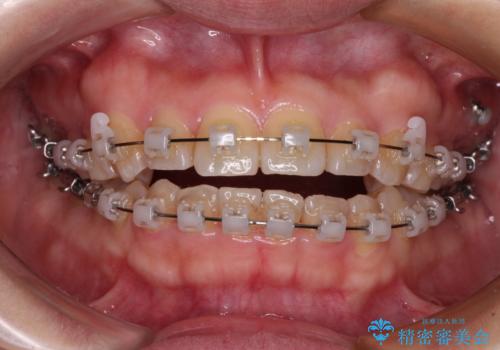

- クリアブラケット

- 1年7ヶ月

- 10-30回

舌の突出癖により上下前歯が開咬となりましたが、舌のトレーニングと顎間ゴムの使用により、元々の被蓋関係に改善することができました。

アンカースクリューを用いて、出っ歯仕上がりを回避し、正中位置も改善することができました。